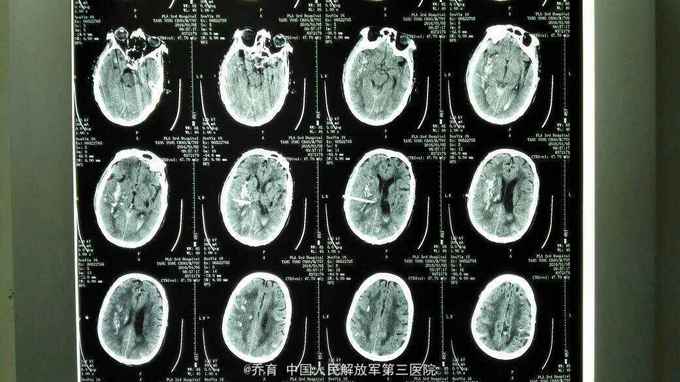

突发意识不清25小时入院,颅脑CT提示右侧基底节脑出血,量约35ml,左侧基底节区脑软化。胸部CT提示慢支,肺气肿,肺大泡,双下肺感染伴纤维化。

患者入院后急诊局麻下行脑内血肿穿刺引流术,术后给予止血,化痰,营养神经,营养支持等治疗。术后第二天复查CT提示出血大部分引出。

对于年龄较大,基础疾病多,出血量较大患者,局麻下行血肿穿刺可明显缩短住院时间,降低并发症,改善愈后。